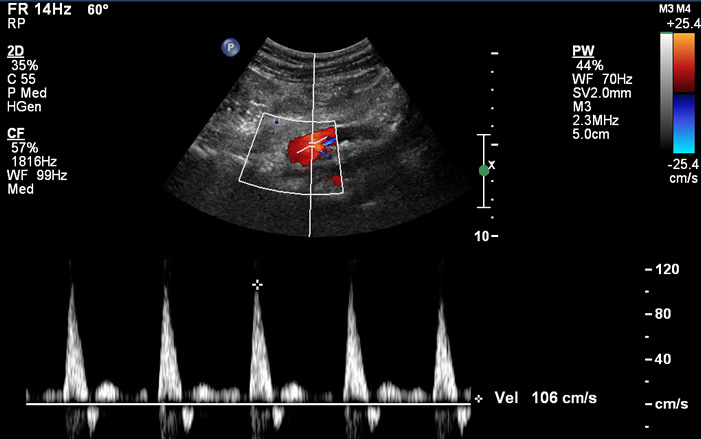

A duplex ultrasound is a non-invasive imaging test that vascular physicians prescribe to see how blood is moving through arteries and veins. It combines the imaging capability of ultrasound with the recording capability of a Doppler ultrasound. A duplex ultrasound can also identify the width of a blood vessel and reveal blockages. For abdominal scans, it examines the blood vessels and flow in the abdomen area to identify any potential blockages, narrowing of vessels or aneurysms.